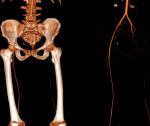

Transthoracic Echocardiography (TTE) showed a biventricular dilated cardiomyopathy (DCM), severe biventricular dysfunction (LV ejection fraction (LVEF): 10%), low cardiac index at 1.20 L/min/m³ with a large intra LV “horseshoe” thrombus, showing also a high heart LV filling pressure with elevated PAPs at 51 mmHg and a dilated inferior vena cava (Figure 2, Figure 3). US troponin and ProBNP were very high at 734 ng/l and 2215 pg/ml respectively. Echo Doppler of lower limbs showed a right popliteal vein thrombosis and an occlusion of femoral axes in the left lower limb (Figure 4). A complement by an angio-CT scan was performed which confirmed the arterial occlusion of femoral axes (Figure 5).

Figure 5: angio-CT scan of lower limb showing an interruption of vascular bed at the level of common femoral artery with partial resumption in the popliteal artery